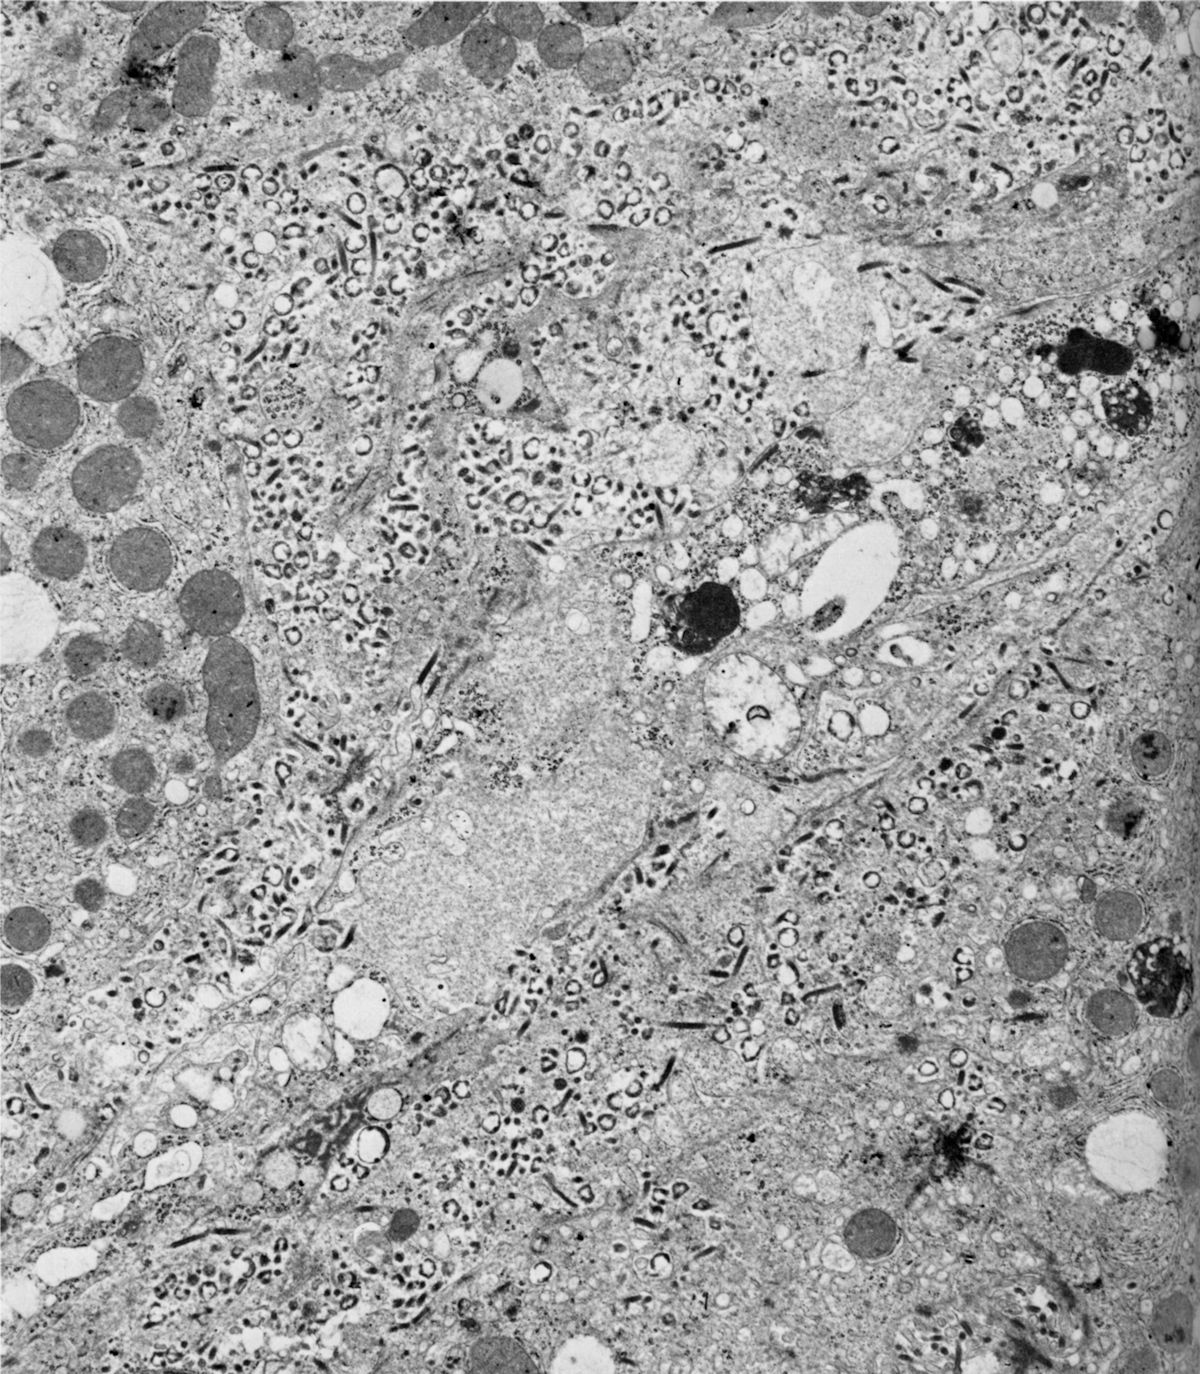

There were 25 primary cases and 6. Time course of Marburg virus strain Popp accumulation and changes in hematological parameters were studied in aerosol infected Mrhesus monkeys. After people have recovered the virus can often be detected for many months in certain body fluids including semen breast milk and urine.

Ebola virus disease symptoms and signs may appear from about two to 21 days after exposure average incubation period is eight to 10 days. Four days after inoculation the virus was detected in the liver spleen blood and thymus. The lungs were the first organ in which the virus was detected after respiratory infection of monkeys.